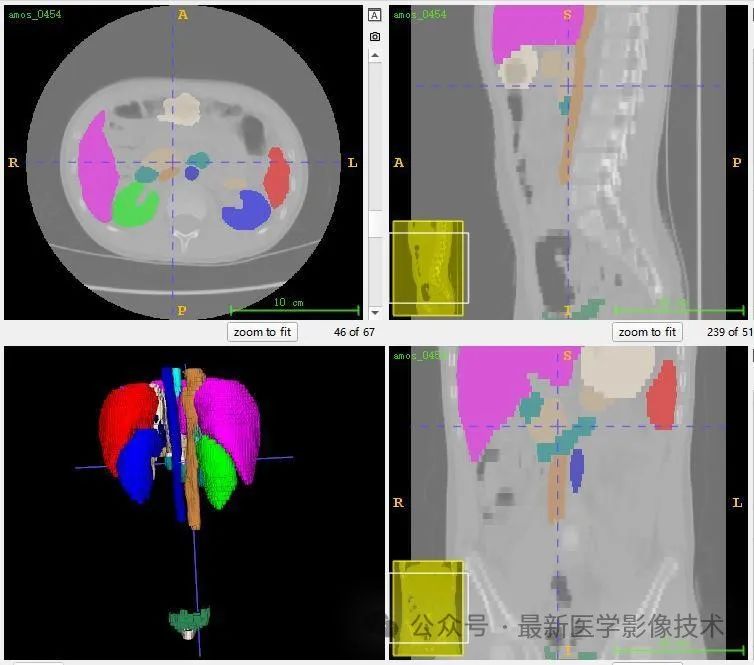

AMOS2022数据集示例说明,提供了 500 例 CT 和 100 例MRI 以及 15 个腹部器官的体素级别注释, 包括脾脏、右肾、左肾、胆囊、食道、肝脏、胃、主动脉、下腹部腔静脉、胰腺、右肾上腺、左肾上腺、十二指肠、膀胱、前列腺/子宫。请注意,某些数据点由于生理移除或由于未扫描身体部位而丢失了某些器官。

共500张CT和MRI,标注了15个器官(脾、右肾、左肾、胆囊、食道、肝、胃、主动脉、下腔静脉、胰腺、右肾上腺、左肾上腺、十二指肠、膀胱、前列腺) /子宫)呈现。请注意,某些数据点由于生理移除或由于未扫描身体部位而丢失了某些器官。

13、测试集分割结果